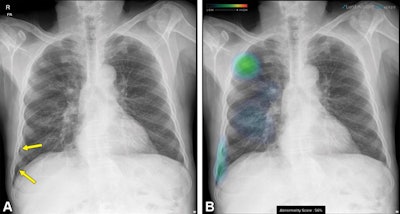

A thoracic radiologist with nine years of clinical experience evaluated the performance of the AI software on heat map or contour line-overlaid images. In addition, the researchers identified pneumothorax cases for which subsequent catheter drainage was required and analyzed the resulting time interval from chest radiography to drainage catheter insertion between the two methods.